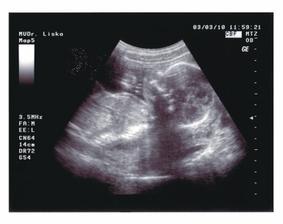

02.03.2010 (20.tt) - Genetický ultrazvuk:máme podrobně prozkoumané miminko, vše je v pořádku, pouze zjištěna mírná dilatace ledvinných pánviček cca 5 mm, dostali jsme doporučení na kontrolní ultrazvuk za měsíc.

03.03.2010 (20.tt) - Na vlastní žádost další ultrazvuk u jiného Dr., abychom dostali mimi na videu - máme úžasný zážitek a ještě úžasnější památku na celý život!